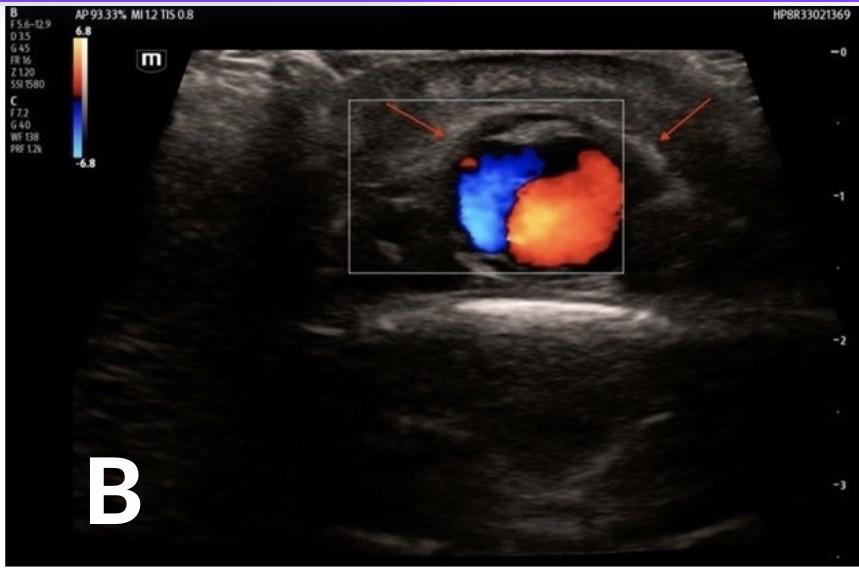

352 Point-of-care Ultrasound Clarified the Diagnosis of an Occipital Artery Pseudoaneurysm After Blunt Trauma

K Nix, S Johnson, D Perling, B Parkinson, H Studebaker, B Foster

355 Point-of-care Ultrasound Diagnosis of Cardiac Myxoma

J Brutico, D Kreider